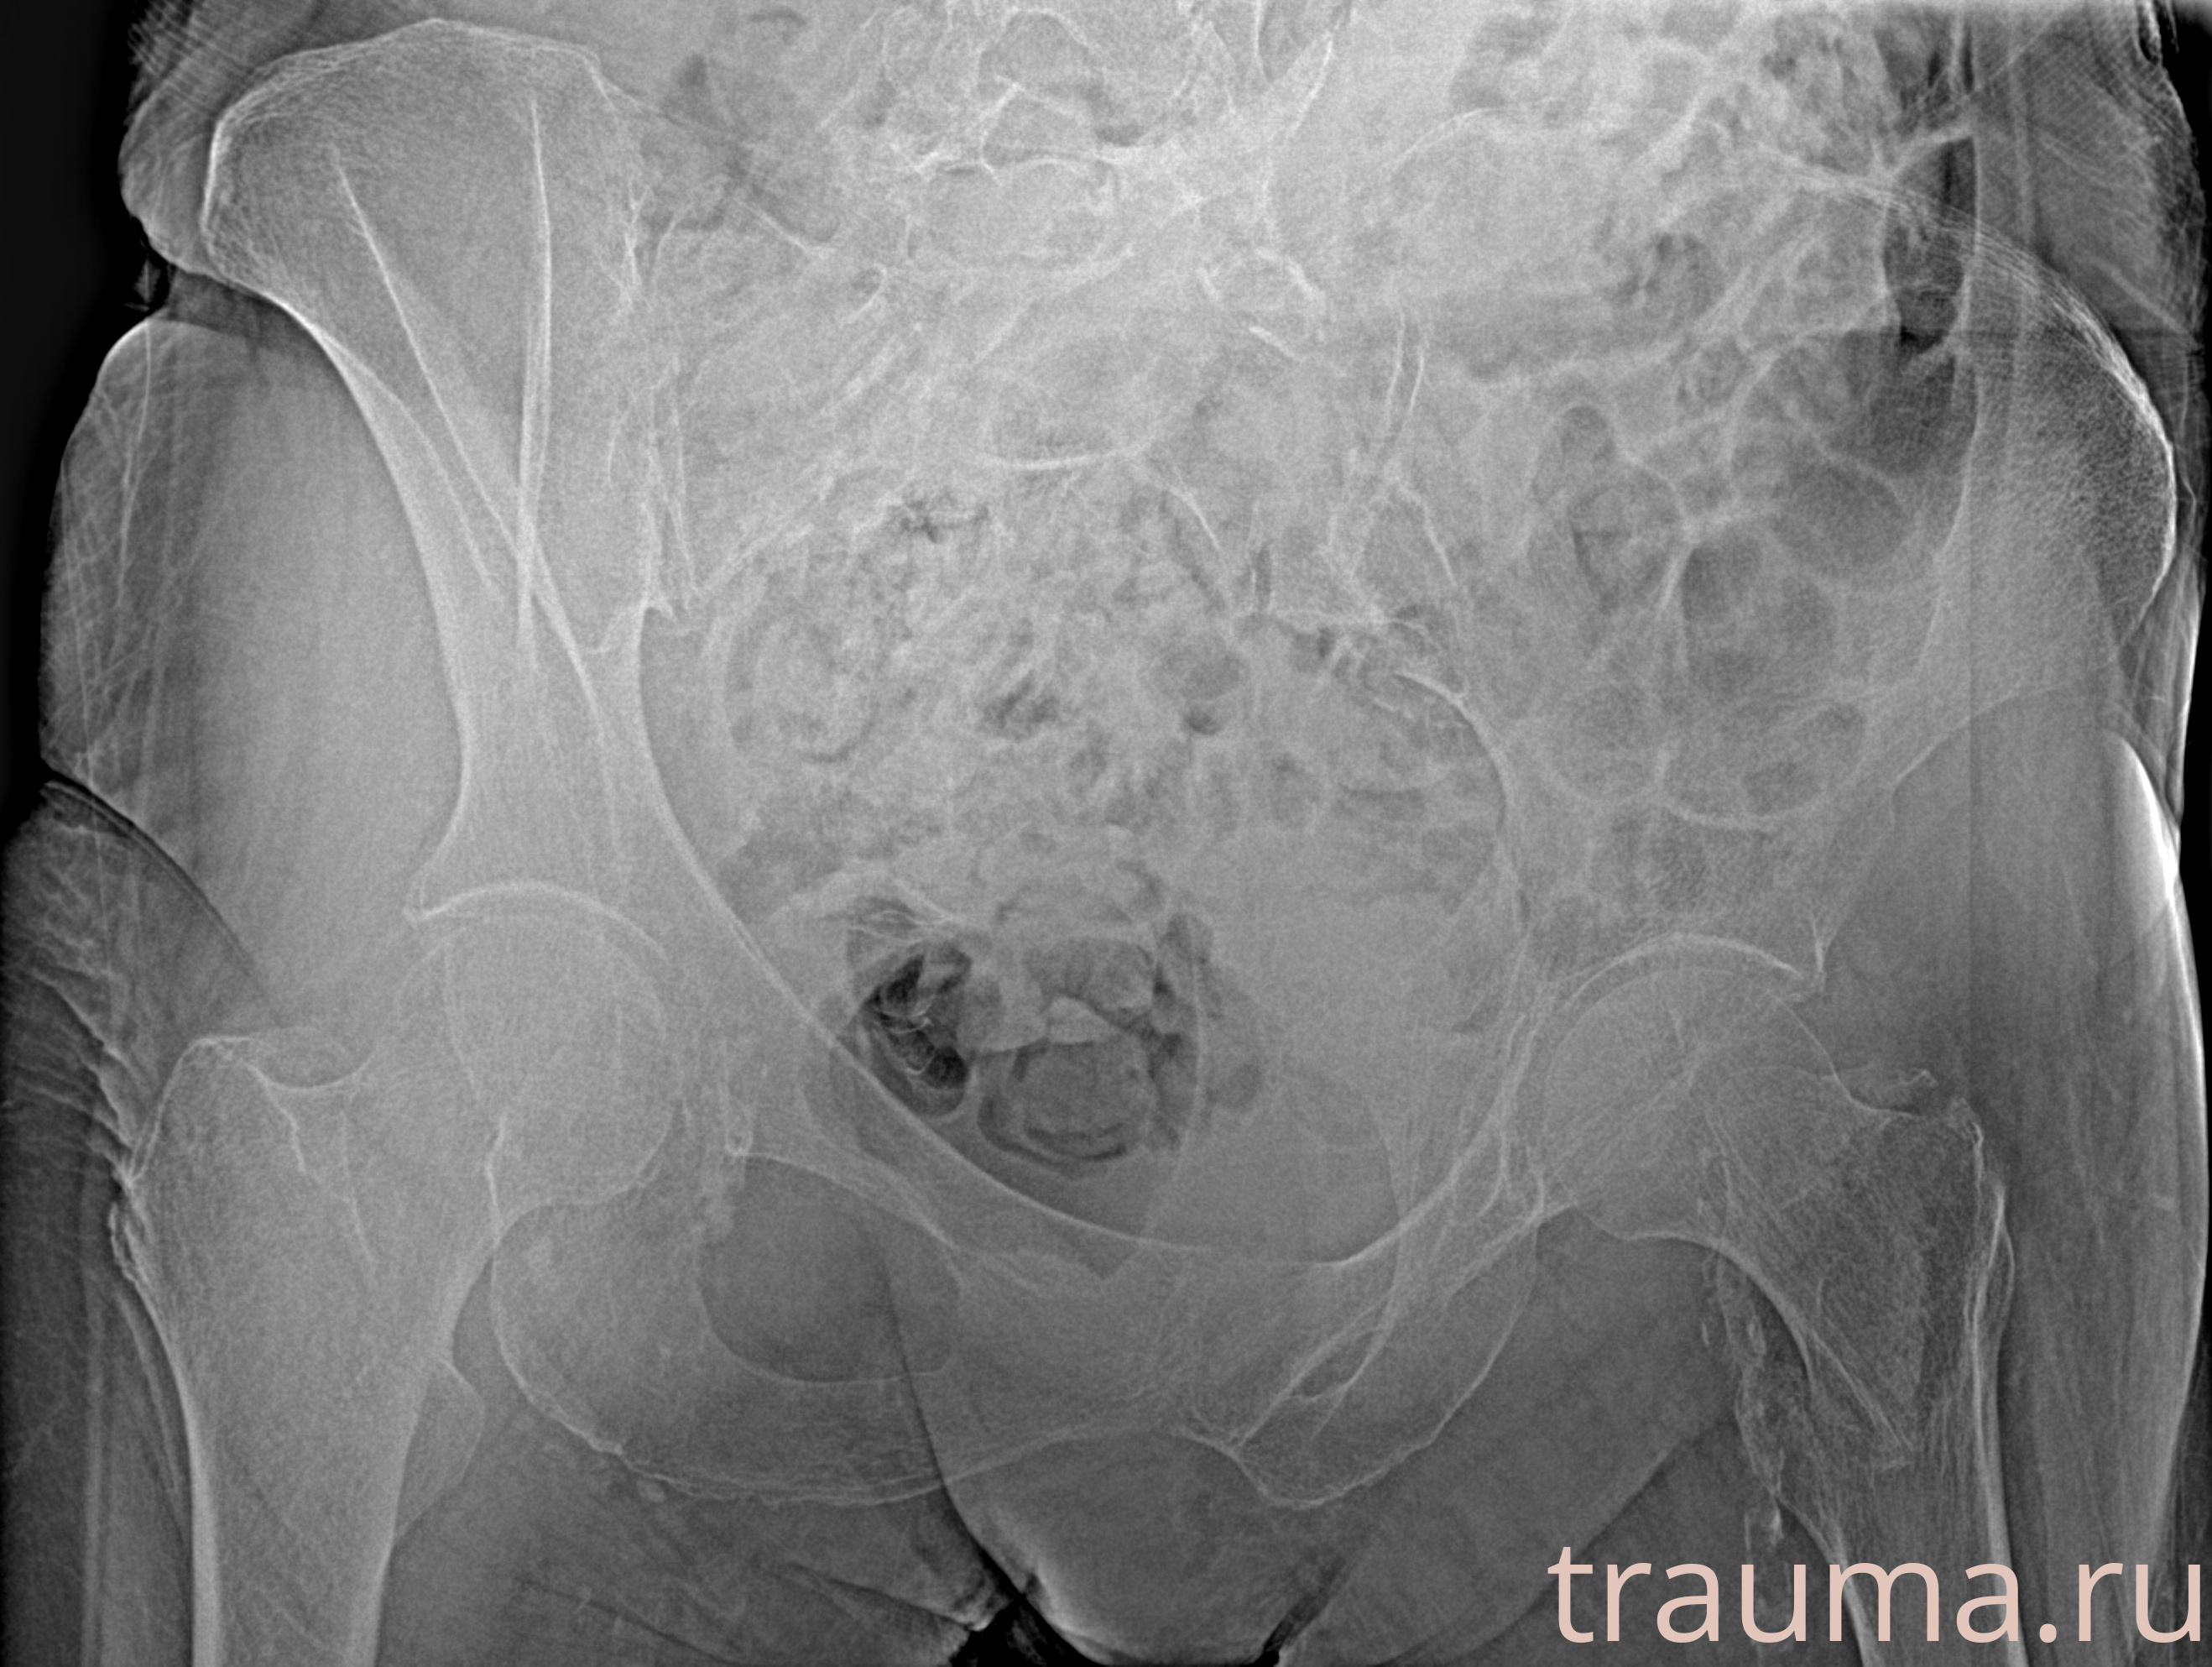

Рентгенограммы

Рентген на дому: по вашему адресу приезжает врач-рентгенолог, травматолог-ортопед с мобильным рентгеновским аппаратом, проводит диагностику травмы или заболевания, делает необходимые рентгенограммы, дает рекомендации по дальнейшему лечению. Получить качественные снимки в домашних условиях возможно благодаря уникальной методике, разработанной МосРентген Центром для института  Склифосовского